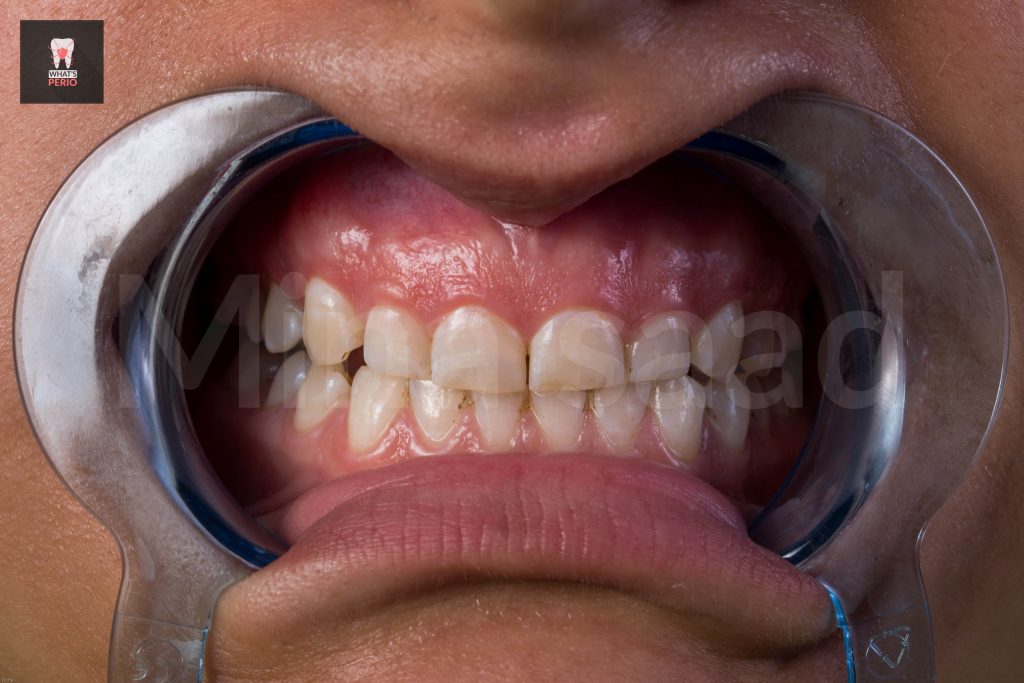

-A 22 years old female come to our clinic seeking a for a solution for her gummy smile .

Clinical examination:

-After excluding other etiologies of gummy smile , it was confirmed that we we have 2 main causes :

1-Hypermobile “hyperactive” lip which is everted more in upper anterior quadrant especially apical to central incisors & lateral incisors.

2-Altered passive eruption. “short clinical crowns”